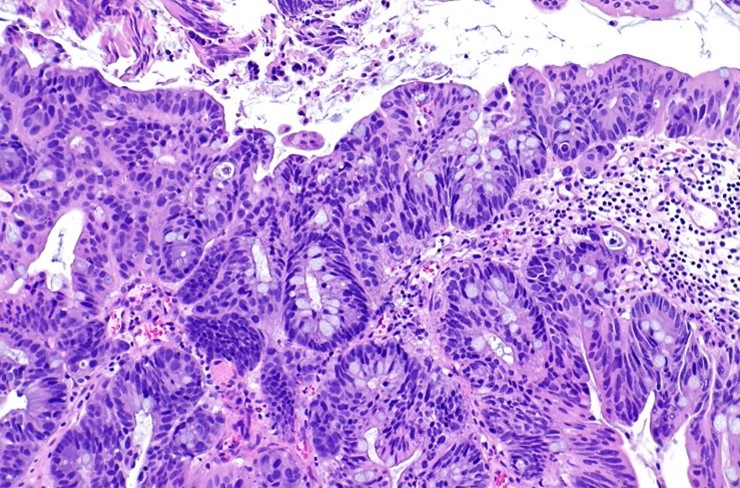

Цитологическое исследование мочи:

Биопсия мочевого пузыря

Морфологическое исследование образцов, полученных после трансуретральной резекции и биопсии, является ключевым этапом в диагностике и определении стратегии лечения рака мочевого пузыря. Строго рекомендуется налаживать тесное взаимодействие между урологом и специалистом по морфологии. В клинике Hadassah самая современная патоморфологическая лаборатория, которая позволяет максимально точно провести диагностику биопсийного материала и точно поставить диагноз.